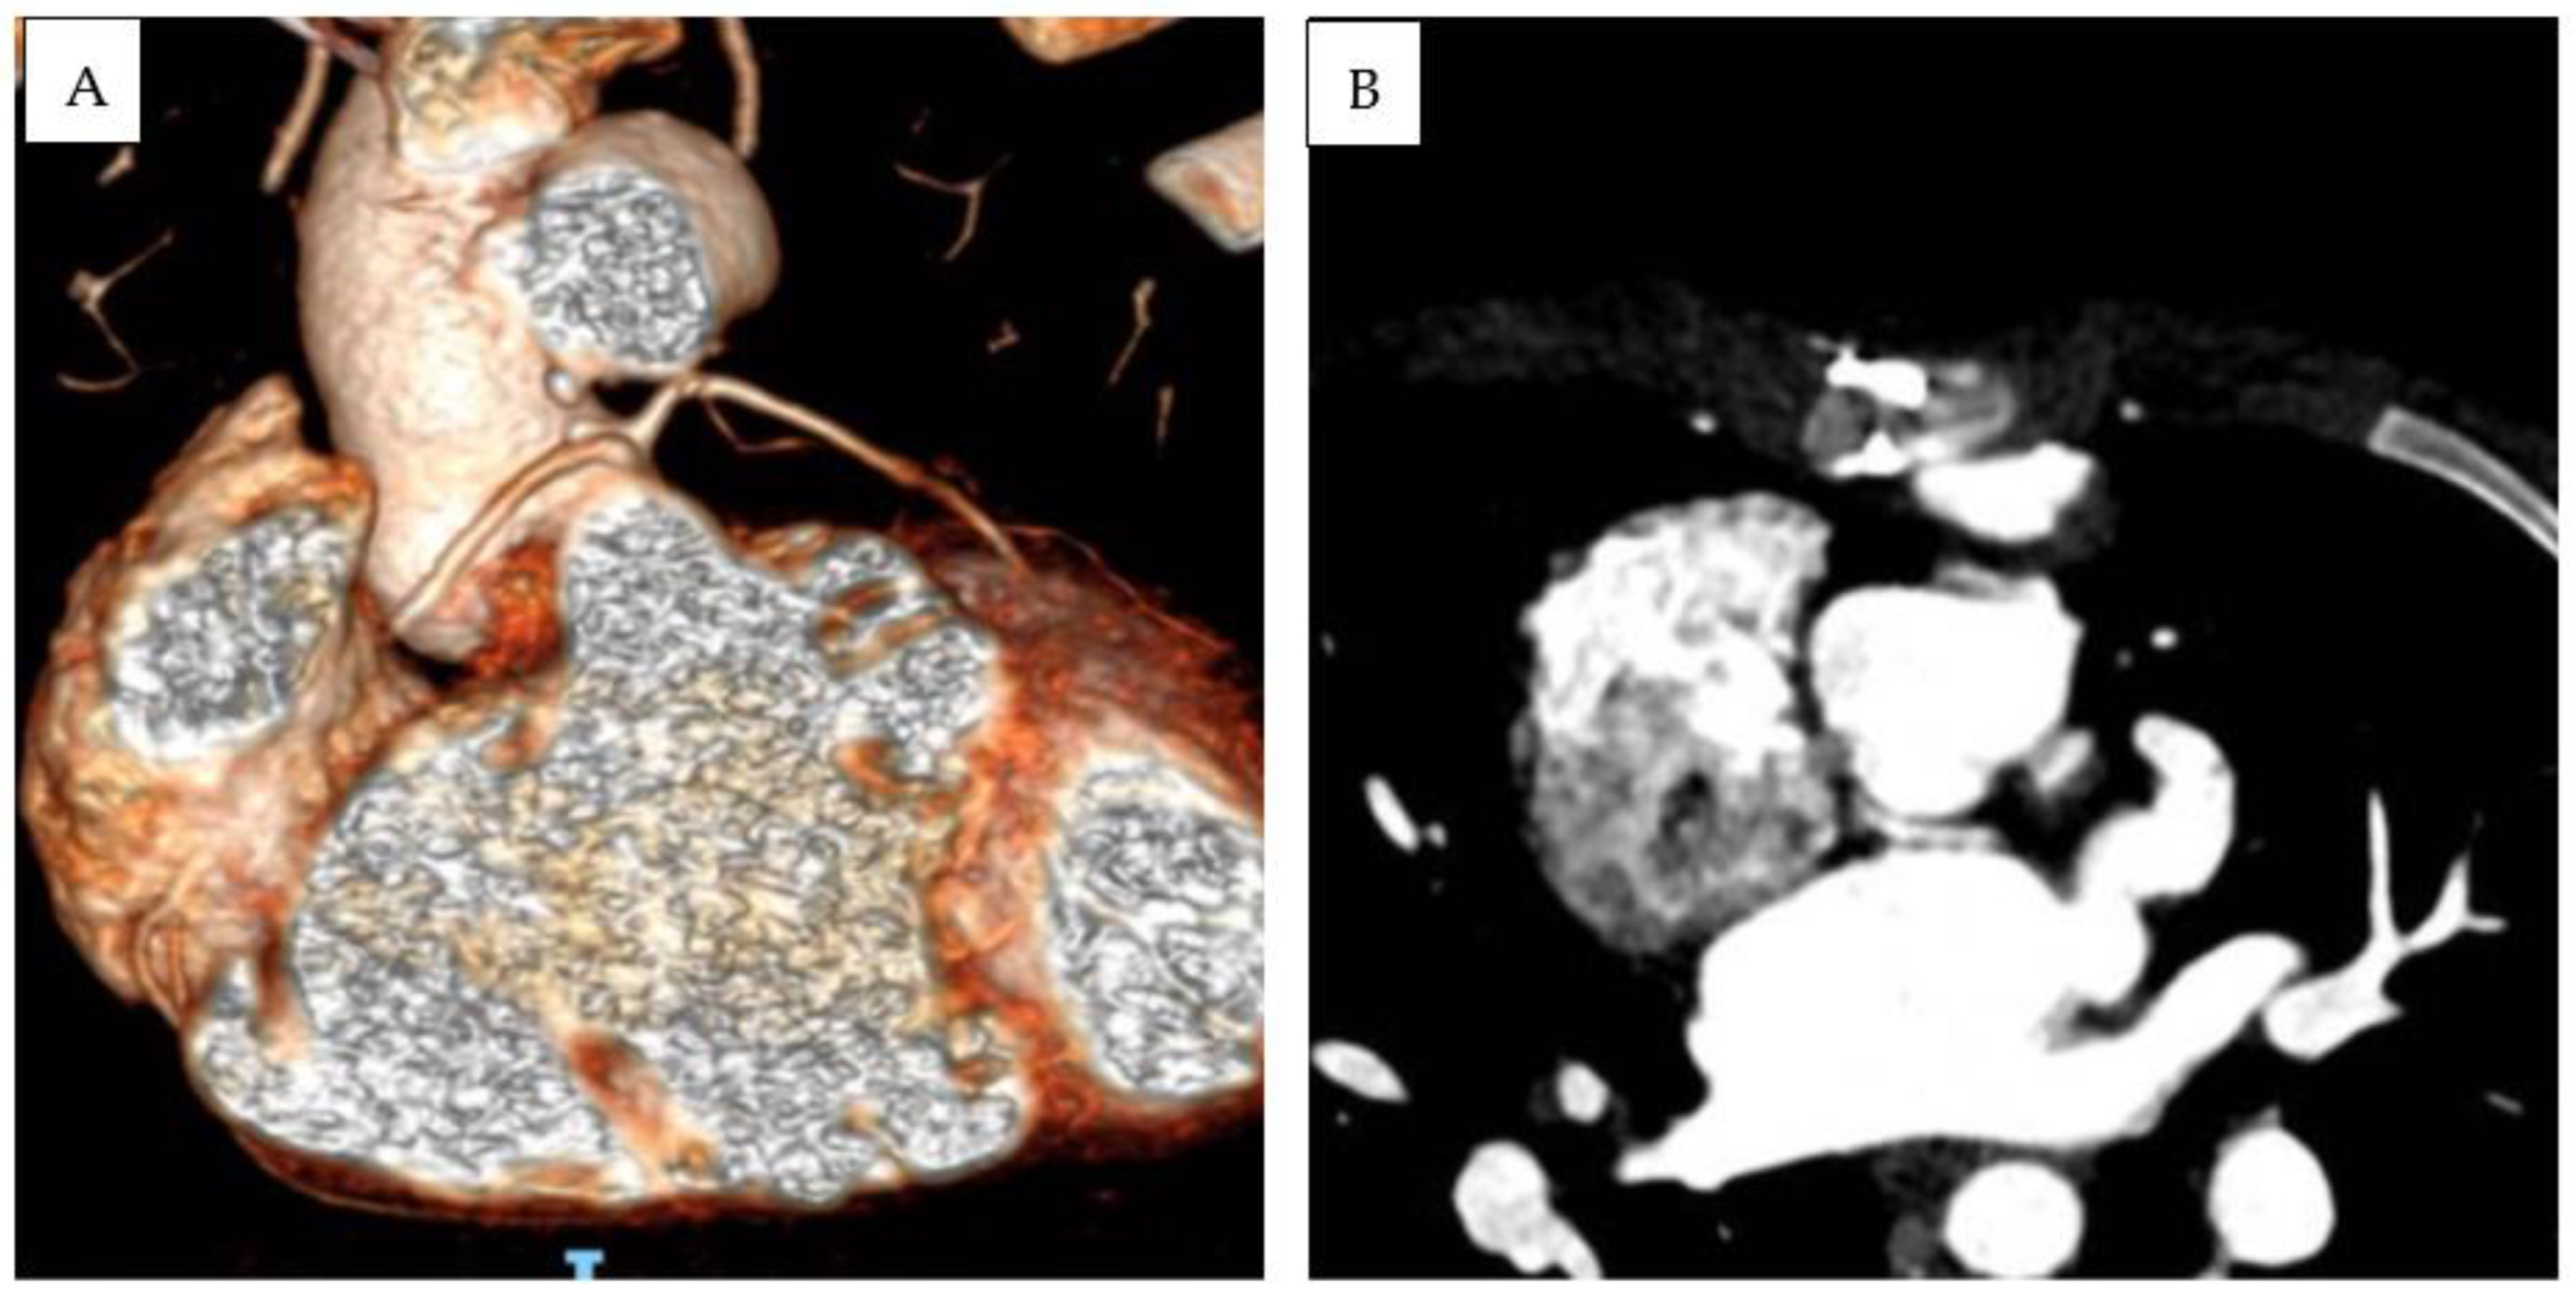

Patient 3 was diagnosed at birth with (S,D,D), DOLV with a subaortic VSD, and PS. The infundibular septum was hypoplasic. The aorta arose on the right and was posterior to the pulmonary trunk. The pulmonary artery was in fibrous continuity with the mitral valve, and a subaortic conus was present. The right coronary artery and left descending anterior artery originated from a single ostium from the anterior facing sinus. LCx was not visualized in echocardiography. A subsequent CT scan revealed that the LCx originate from the posterior-facing sinus, with a retroaortic course and slit-like origin (Figure 2). After the initial B-T shunt palliation, a Rastelli-type operation was performed at 1 year of age (10 kg), the interventricular communication was closed, and a bicuspidized pulmonary homograft was sewn in the right ventricular outflow tract. LPA was enlarged with the interposition of a Dacron patch. After a 6 year follow-up, severe degenerative stenosis of the RV-to-PA conduit was present; nevertheless, percutaneous conduit dilatation was contraindicated due to coronary abnormality. LCA and RCA were, respectively, caudal to supravalvular and subvalvular segments of the RV-to-PA conduit. After multidisciplinary discussion, an aortic homograft (25 mm) was implanted. At the last follow-up (total f.u. time 10.2 years), the patient was in good clinical status and presented moderate right ventricular outflow tract obstruction (gradient from tricuspid regurgitation at least 50 mmHg, between 50% and 75% of systemic arterial pressure). No arrhythmias were detected during follow-up, except for low-burden premature ventricular beats with superior axis and rBBB morphology, present at rest and during recovery, and disappearing with maximal exercise.

Figure 2.

Three-dimensional (A) and MPR-angio CT scan (B) documenting anomalous coronary anatomy in Patient 3. Due to the strict relationship between RV-to-PA conduit and RCA and LCA, percutaneous conduit dilatation was contraindicated.